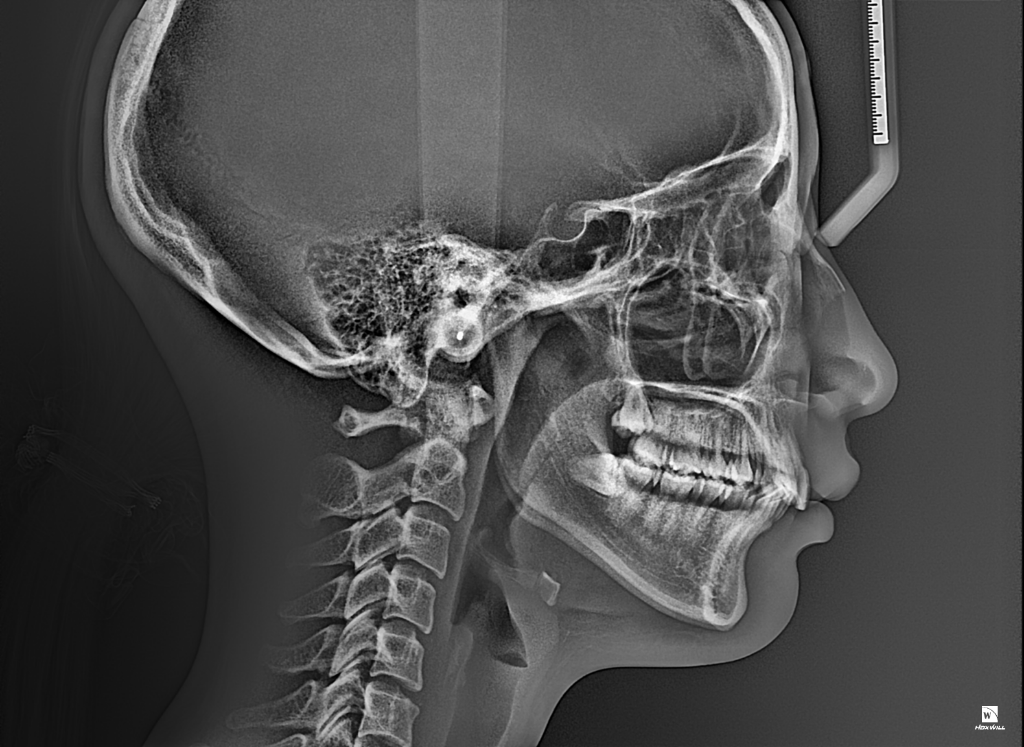

위, 아래 어금니가 맞물리는 상태를 보면 II급 부정교합의 상태이고 위 앞니가 아래 앞니를 정상보다 조금 더 많이 덮고, 더 튀어나온 것 같습니다.

성인이시기 때문에 발치 교정이 가장 효율적이면서 간단한 교정치료방법일 것으로 생각됩니다. 일반적인 경우 위 소구치(작은어금니)를 하나씩 발치하고 그 빈 자리를 이용해 앞니를 뒤+위로 밀어넣고 교합도 I급으로 맞춰주고 할 수 있습니다. 교정치료에 있어서 필요하다면 매복사랑니 발치를 할 수도 있습니다.

돌출된 앞니는 외상 시 충격을 좀 더 받을 가능성이 높고요, 현재 어금니가 맞물리는 II급 부정교합의 형태가 치아가 정상적으로 맞물리는 것에 영향을 주어 치아가 보통보다 빠르게 마모될 수도 있고 파절될 수도 있습니다. 이러한 교합상태는 턱관절에 긴장을 불러일으켜 턱관절 질환, 안면비대칭을 유발할 가능성도 있습니다.